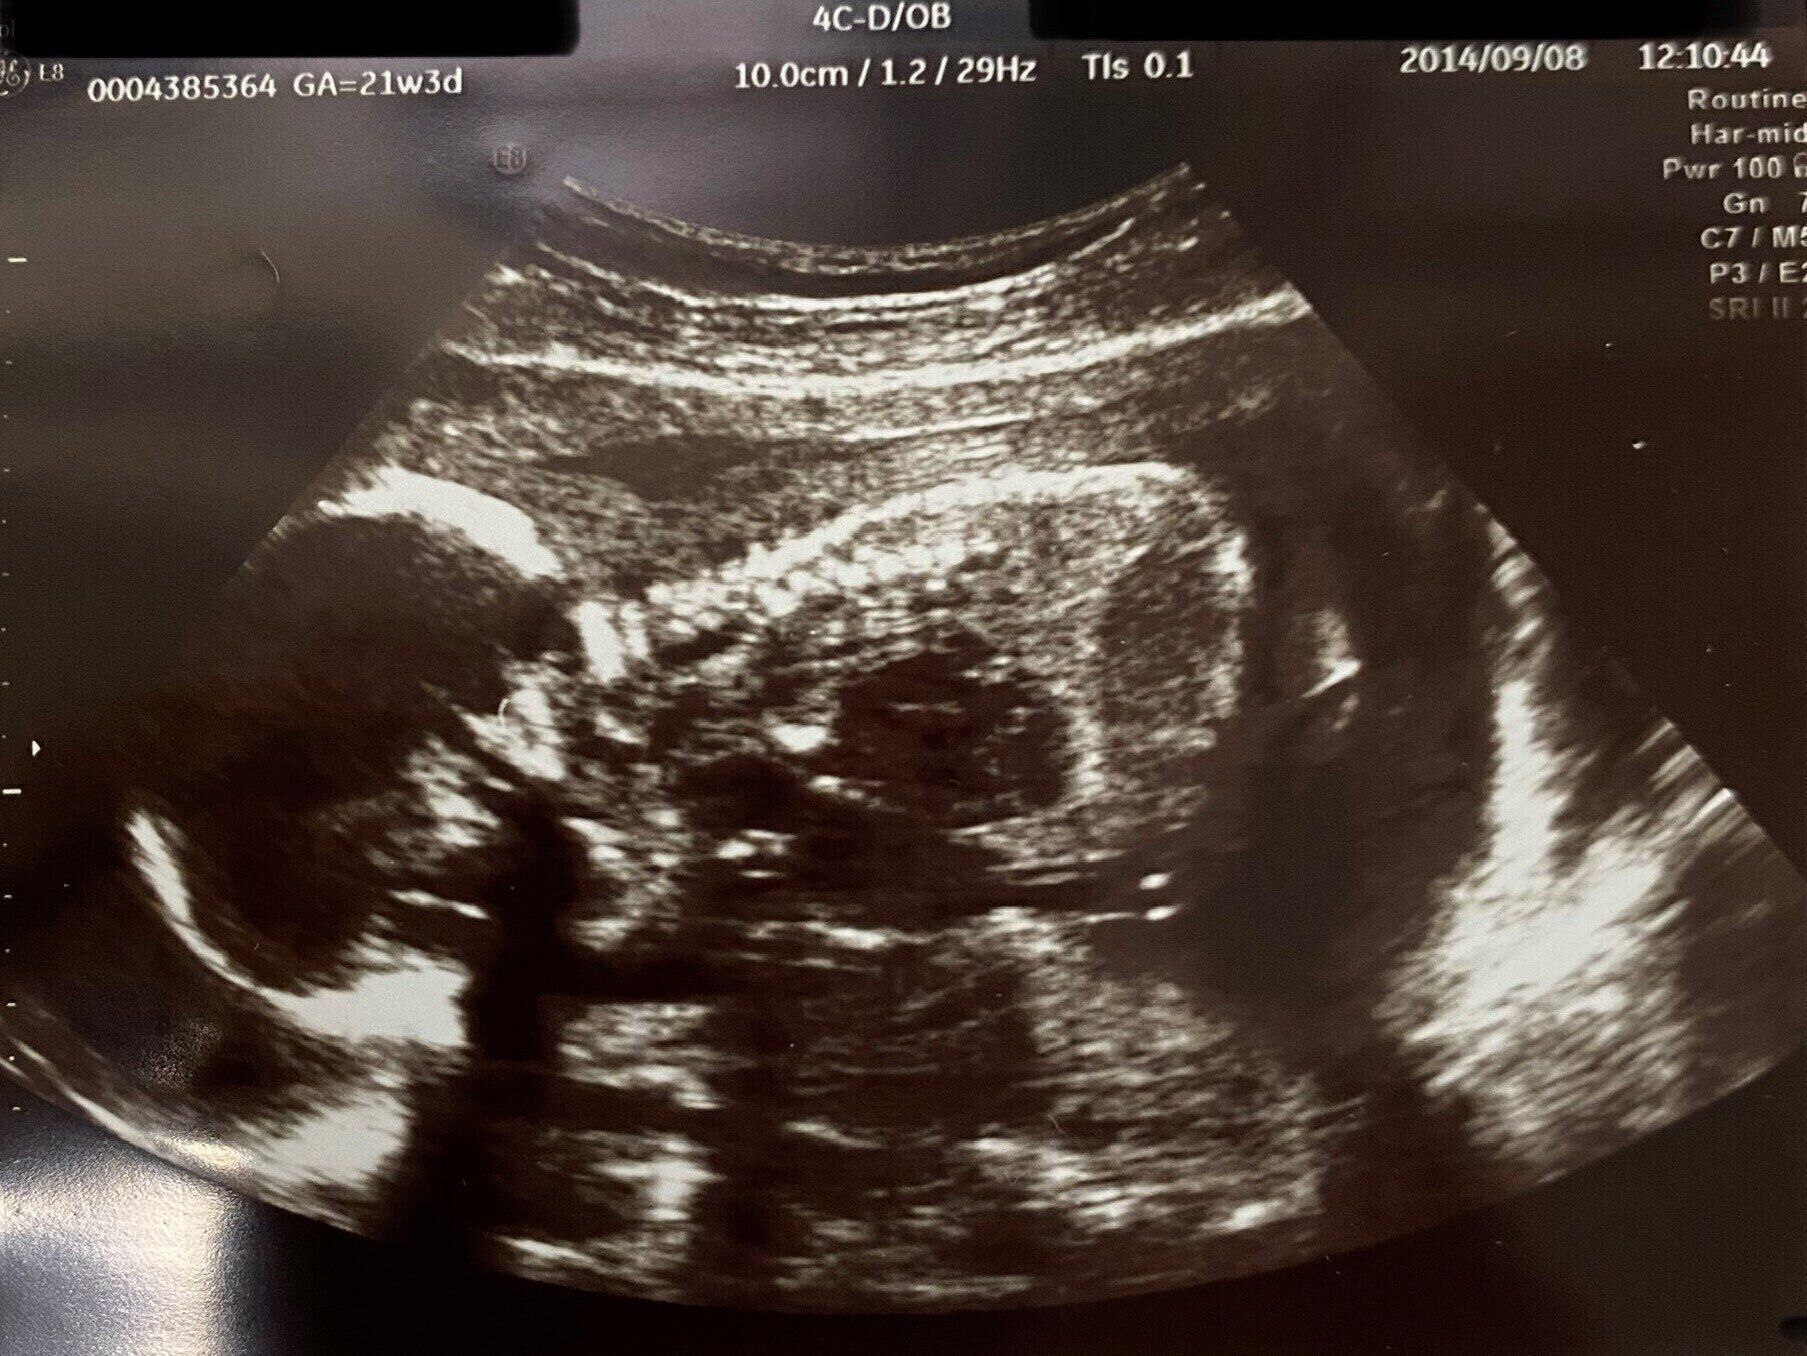

「妊娠21週3日の妊婦健診で、“赤ちゃんが小さい”と指摘されて…。体重は319g、胎児発育曲線の下限ギリギリでした。それ以外はとくに問題なかったんですが、不安になって“21週3日”“赤ちゃん小さい”“319g”などとキーワードを入れて検索したんです。